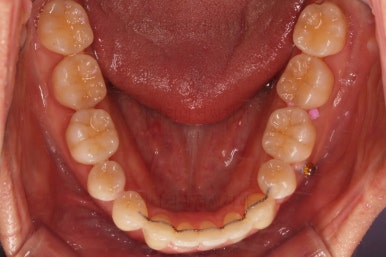

부산비수술교정 키다리아저씨치과에 처음 내원하셨을 당시의 입 안의 모습입니다.

아래 앞니에 결손치아가 하나 있네요. 송곳니-송곳니 사이에 앞니가 4개가 있어야 정상이지만 이 분은 3개에요. 의외로 아래앞니 하나 혹은 두개가 없는 경우가 굉장히 많답니다.

갯수가 맞지 않다보니 치열의 중앙도 맞지 않고 비대칭이 됩니다.

그리고 주걱턱이기 때문에 당연히 아랫니들도 앞으로 나올 수 밖에 없어 윗니보다 앞에 나와있어요.

이를 반대교합이라고 합니다.

어금니의 맞물림도 연쇄적으로 몇 칸씩 밀려있는 양상이라 효율도 좋지 못하고 치아의 건강에도 좋지 못해요.

이 분의 경우에도 전반적으로 잇몸이 약해져있을 수 밖에 없어요. 보시면 아시겠지만 잇몸 퇴축이 심해서 치아들이 길쭉길쭉해 보이죠.